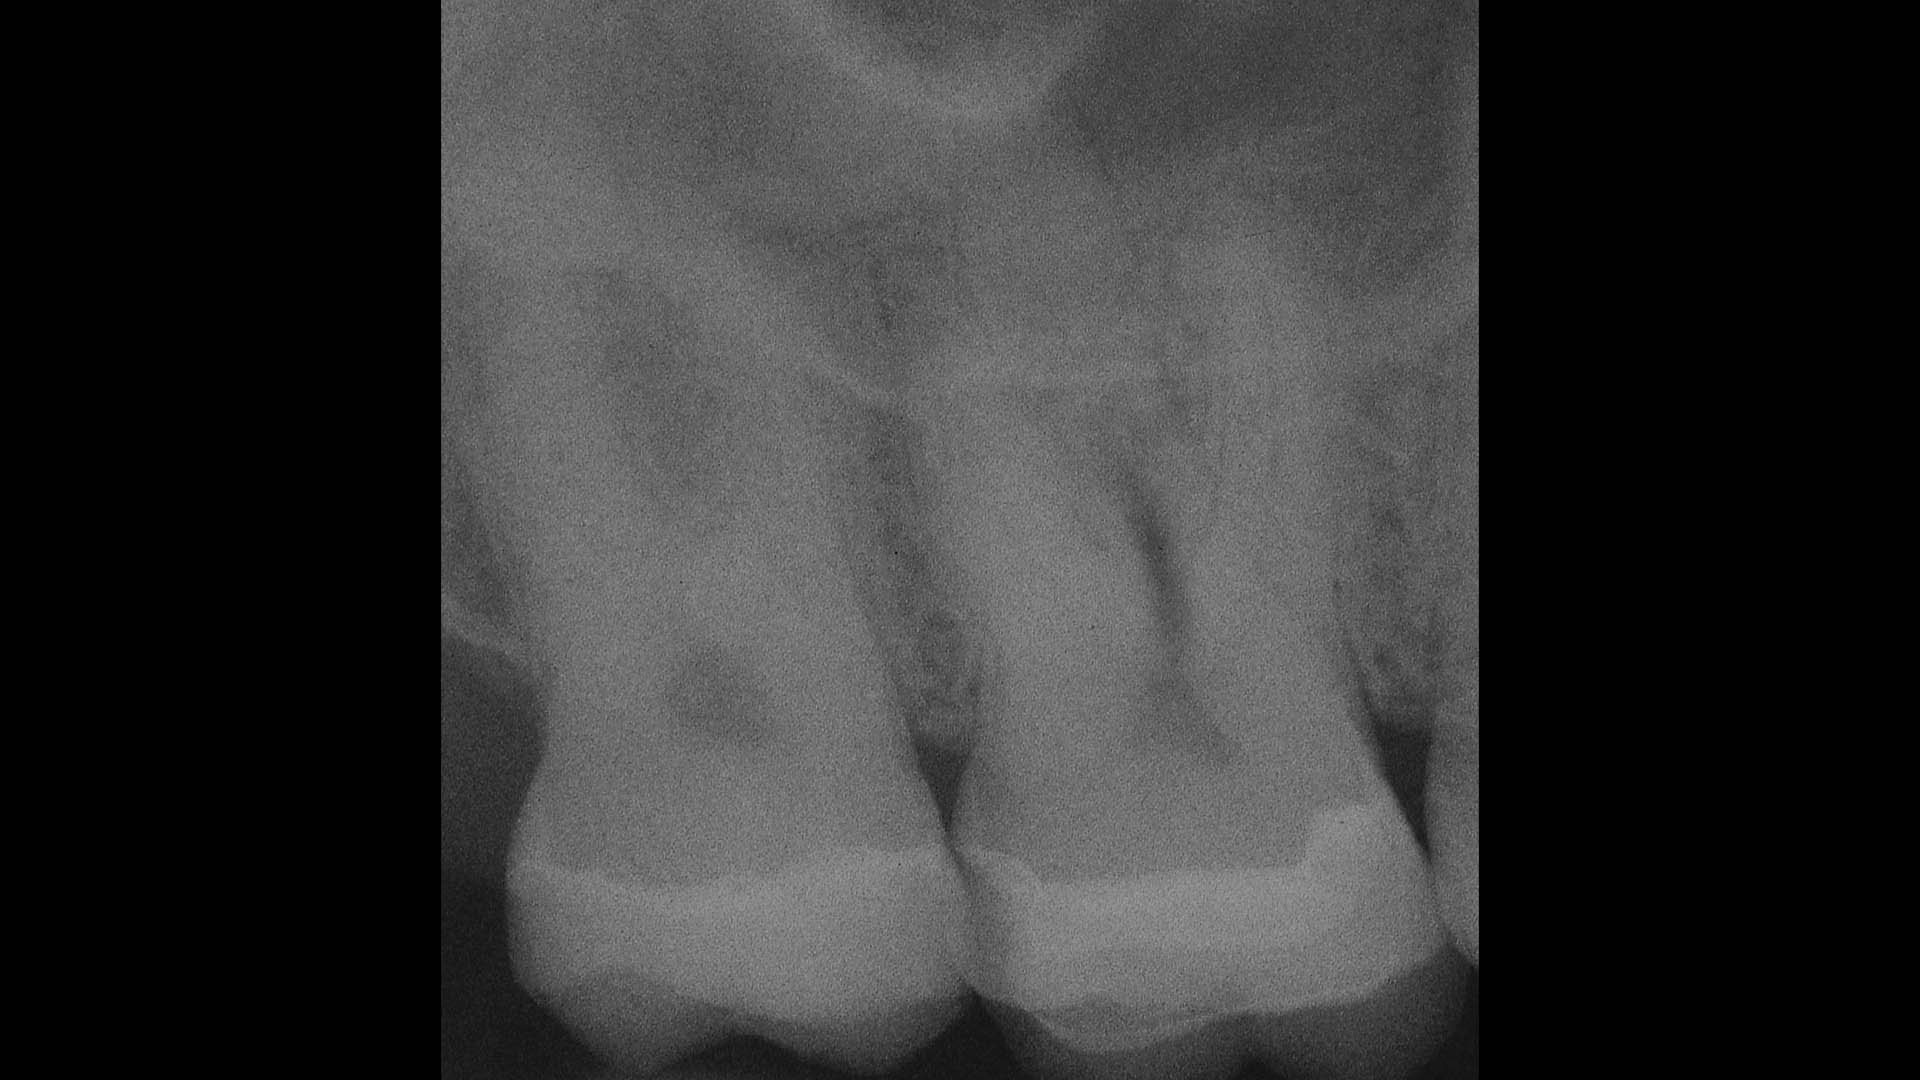

Take a glimpse into the magic of Coral Gables Dentistry through our before and after pictures. See firsthand the incredible smile makeover transformations that have brought confidence and joy to our patients.